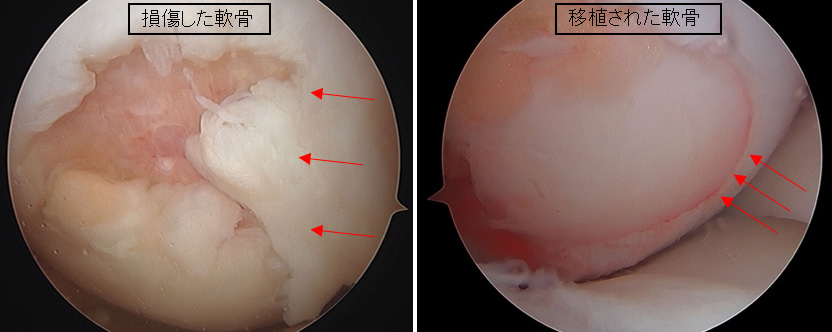

③ 自家骨軟骨柱移植術(じかこつなんこつちゅういしょくじゅつ)

【図2 自身の身体から採取した移植前の骨軟骨柱

(先端の白い部分が軟骨でその他の部分が軟骨下骨)】

モザイクプラスティなどとも呼ばれています。自身の機能破綻を生じしにくい部分から軟骨と軟骨下骨を円柱状に採取し、それを軟骨欠損部へ移植させることで損傷部位の軟骨修復を図る方法になります。この方法は比較的大きな軟骨損傷にも適用できるとされていますが、自身の正常軟骨を使用するため、採取できる軟骨の量に限界があります。(図2. 3. 4)

【図3 関節鏡でみえる離断性骨軟骨炎 その1

(左:手術前の損傷した軟骨、右:骨軟骨柱移植術後の軟骨)】